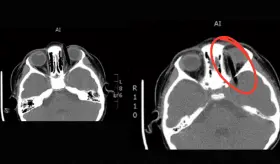

El crecimiento progresivo de la masa y la limitación mecánica del movimiento ocular fueron indicios clave que llevaron a profundizar en el estudio.

Los tumores presentaron un patrón histológico casi idéntico y localizado en el área de contacto directo con el dispositivo, lo que sugiere un posible efecto relacionado con la exposición prolongada a la radiación electromagnética.